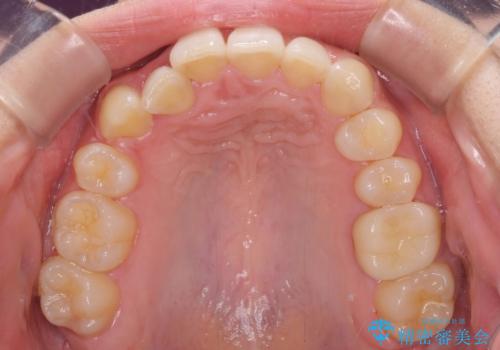

- 上顎の重なっている前歯を気にして来院された患者様です。

八重歯改善には抜歯が必要で、八重歯の移動量が多く、更には右側にずれている正中を改善する必要がありました。

インビザライン単体での治療は困難と判断し、補助装置により八重歯移動後にインビザラインを用いることとしました。

インビザラインでは治療期間が延びることが予想されたため、ワイヤー矯正を提案しましたが、セラミッククラウンが多く、壊すあるいは傷が付く可能性があることから、長期間であってもインビザラインを選択されました。